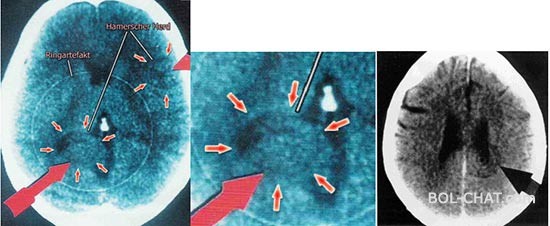

As at that time worked as chief internist at the clinic for cancer in Munich, he began to study the history of all cancer patients and compares them with its findings. I discovered not some striking similarities. In fact, all patients before the onset of cancer also had some stressful and dramatic experience, a greater or lesser intensity, in any case unexpected. Assuming that all the experiences of the body registered in the brain, Hamer was analyzed and all CT scans of the brain (made computed tomography) and all of them compared with his. What he found all surprised. At every CT imaging is detected on something that was read as a series of concentric circles like rings in the water that is formed upon insertion of pebbles.

Hamer-Arista-ct-stringThis lesion, which is registered in the brain CT scanner was in different patients at different locations and different intensity, but was always there with a characteristic concentric circles.

Interestingly, as doctors who read CT findings and earlier this concentric pretzels as spotting, but they thought that it was an artificial creation that was created in the apparatus but this did not attach special significance.

Are invited engineers from Siemens (whose camera was in use) and there have been more different images from multiple angles and these lesions are always seen in the same place. So this is the focal point visible on CT was named Hamer focus or HH (Hemer Herde).

What is further noted that it was the location of the brain lesions always been in the region of the brain that is correlated with the body on which to create a tumor or ulcer, and always it was a body whose work is controlled by the brain.